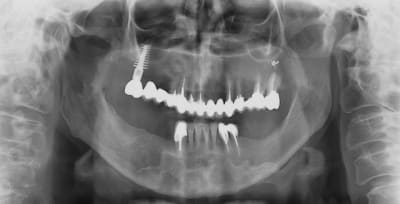

17/06/2009 à 21h12

pour ce vendredi, expansion verticale en bas à gauche, pas simple mais...

Implants à gauche...et à droite ?

Paro avancée sur 42 à 32 ??

Joli implant disk zone 16 avec bridge dent-implant.

Implants à gauche et à droite, c’est un cas d’expansion horizontale droite et gauche que je dois faire en Novembre en directe (pour des confrères Russes), et vendredi je prépare le site à gauche, pour avoir une hauteur correcte pour remplacer ensuite 35/36.37.

En principe je ne poserais pas les implants vendredi, sauf si le site est nickel pour.

Pour l’implant du haut ce n’est pas un disk, mais un D4 de Tatum (impacté) 7,5 x 4X20mm (en coupe il a une forme de D) extrême résistance et avec ce type d’implant il n’y a pas de soucis implant/dents pour les bridges.

Celui-ci doit avoir une quinzaine d’année je n’ai pas la fiche ici, si je peux je passerai le scan.